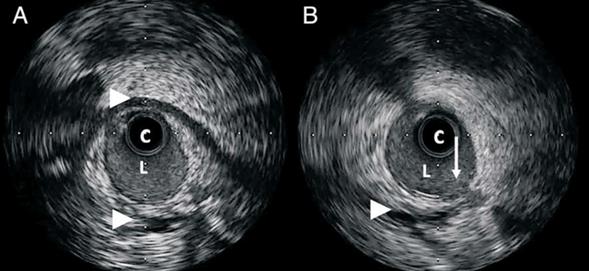

Se interpreta que esta imagen podría corresponder a una DCE, y, dado que no es concluyente, se decide realizar IVUS. En este se observa la presencia de un hematoma intramural extenso que determina una disminución del calibre arterial mayor a 50%. A su vez, se visualiza un sector que comunica la luz del vaso con el hematoma, lo que corresponde a la presencia de desgarro intimal (figura 2). Dado que la paciente se encontraba en ese momento asintomática, y sin evidencia de isquemia miocárdica en curso, se decide continuar con tratamiento médico en base a ácido acetil-salicílico (AAS), clopidogrel, estatinas, inhibidores de la enzima convertidora de angiotensina (IECA) y betabloqueantes (BB). La paciente evoluciona favorablemente, no presenta complicaciones durante la internación, y es dada de alta a los cinco días del ingreso.

Presentamos el caso clínico de una paciente joven con un IAMSEST, se le realizó CACG de urgencia y en esta se observó una imagen sugestiva de DCE, por lo que se decide realizar IVUS. Con este método se evidencia un extenso hematoma intramural que compromete la luz del vaso y se comunica con este mediante un desgarro intimal.

Frente a la imposibilidad de confirmar el diagnóstico mediante CACG, tiene indicación el uso de técnicas de imagen intracoronaria. El IVUS, así como la OCT, pueden ser utilizados para el diagnóstico de DCE. Esta última presenta ciertas ventajas sobre el primero gracias a su mayor resolución espacial, ya que permite visualizar el endotelio y así diferenciar el desgarro intimal, la luz falsa, la hemorragia intramural y la presencia de trombo.

En el caso que se presenta se sospechó una posible DCE, por lo que se realizó IVUS, donde se observó el hematoma intramural y se logró visualizar el sitio de desgarro intimal, hecho poco frecuente con esta técnica a diferencia de la OCT.